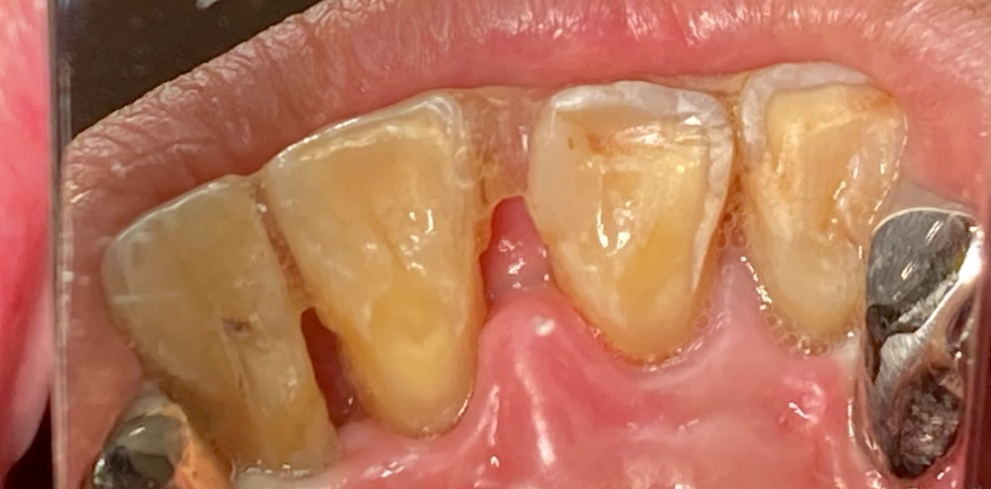

【治療開始時の状態】

●排膿: 前歯と奥歯の歯ぐきから、指で押すと膿が出る状態。

●動揺: 歯を支える骨が溶けているためグラつきがあり、ワイヤーで隣の歯と固定して維持している状態。

●骨の状態: X線検査にて、歯を支える歯槽骨の著しい吸収(骨が溶けて減っていること)を確認。

【診断】

重度歯周炎(広汎性重度慢性歯周炎の急性発作を含む)